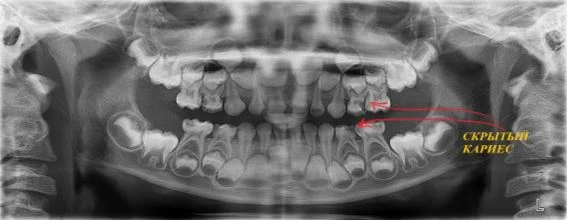

- вероятное наличие невидимых при обычном осмотре кариозных полостей;

Давайте сравним снимки зубов, сделанные при помощи визиографа (слева), и при помощи компьютерной томографии (справа).

Как говорится, ощутите разницу. КТ - гораздо более точная и своевременная диагностика.